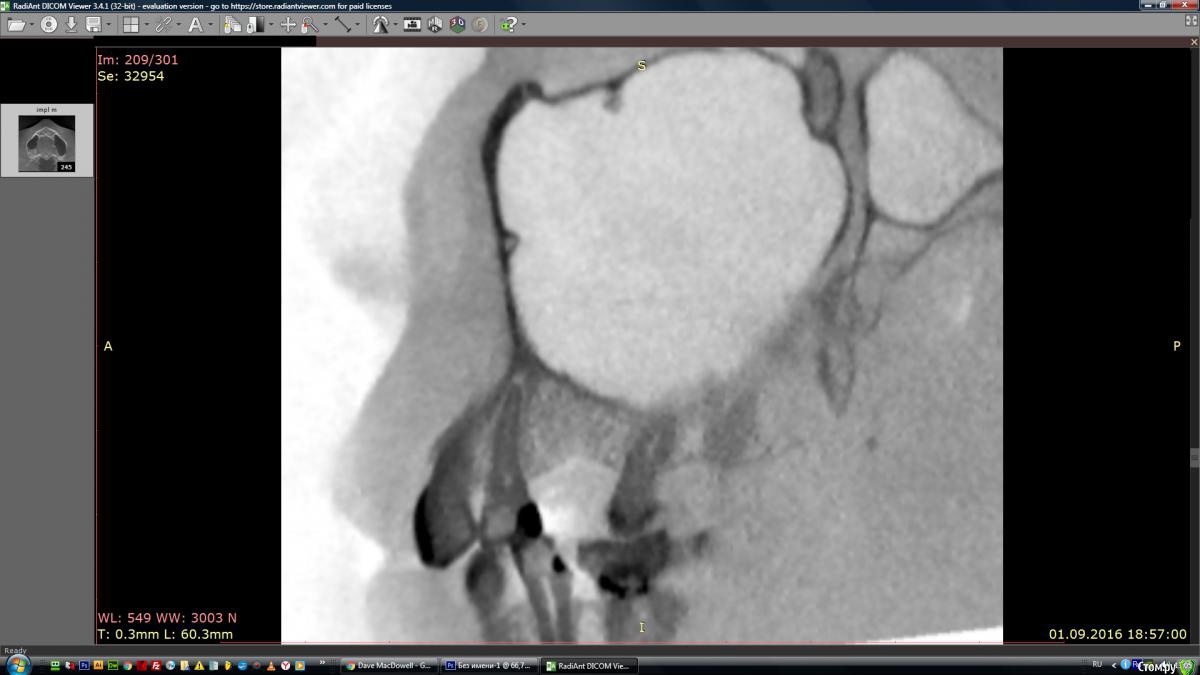

marinamarina Опубликовано 16 октября, 2016 Автор Поделиться Опубликовано 16 октября, 2016 (изменено) Прилагаю фрагмент КТ. Изменено 16 октября, 2016 пользователем marinamarina Ссылка на комментарий

IvanK Опубликовано 17 октября, 2016 Поделиться Опубликовано 17 октября, 2016 Большая вероятность того, что какой-то вид наращивания кости потребуетсянужно оценить не только высоту костной ткани до верхнечелюстной пазухи, но и ширину Ссылка на комментарий

marinamarina Опубликовано 17 октября, 2016 Автор Поделиться Опубликовано 17 октября, 2016 Большая вероятность того, что какой-то вид наращивания кости потребуетсянужно оценить не только высоту костной ткани до верхнечелюстной пазухи, но и ширинуСпасибо за ответ! Про синус лифтинг я знаю, я имею в виду пересадку костного блока в место травмы, попробую выложить поперечный срез. Ссылка на комментарий